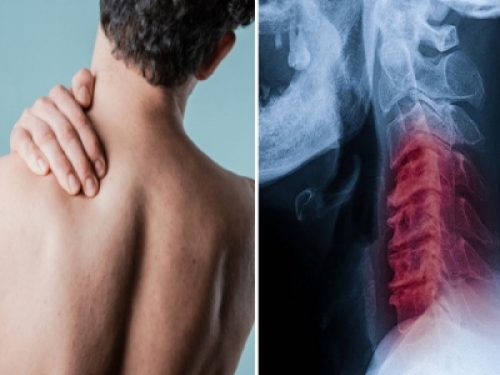

喬許被岳父帶往醫院急診,到院時已半身麻掉、有複視症狀。院方血管攝影結果發現,他的頸動脈分離,造成腦溢血,趕緊注射TPA靜脈血栓溶解劑治療

後來又轉至大醫院的加護房,待了4天才來到普通房,主治醫生指出,喬許應該是在扭轉脖子時,牽扯到了頸部動脈,才會導致動脈分離,血栓在患部形成後,堵塞了血管